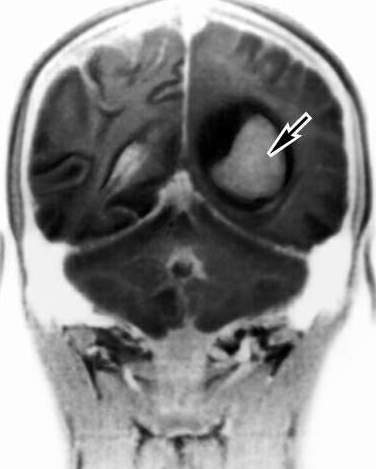

Менингиома головного мозга — наиболее распространенная доброкачественная опухоль мозга, возникает из его оболочек, характеризуется очень медленным ростом. Обычно она наблюдается у пожилых людей, у женщин в два раза чаще, чем у мужчин. Злокачественные опухоли, например, медуллобластома, растут намного быстрее. Кроме того, они разрушают и близлежащие ткани. У взрослых злокачественные образования развиваются в полушариях и коре головного мозга, у детей - в задней черепной ямке.

Степень тяжести заболевания зависит от того, является ли опухоль операбельной. Если даже она носит злокачественный характер, но локализация позволяет провести операцию по ее удалению, то результаты лечения будут хорошими, и больной выздоровеет. Прогноз хороший и в случае менингиомы. Дело в том, что она растет очень медленно, и, как правило, операция по ее удалению успешна. Часто после операции по удалению опухоли проявляются нарушения физических и психических функций. Иногда пациенту приходится заново учиться выполнять простейшую повседневную работу.